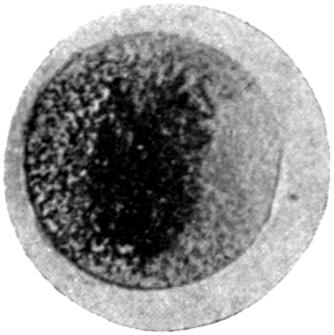

Plate IV. 276

[43]

REFERENCES.

[1] Cloetta: Dixon Mann’s Forensic Medicine and Toxicology, p. 463.

[2] Oliver, Sir T.: Diseases of Occupation, p. 142.

[3] Goadby, K. W.: Departmental Committee on Lead Poisoning, etc., in China and Earthenware Manufacture, Appendix No. XXV.

[4] Meillère and Richer: Meillère’s Le Saturnisme. Paris, 1903.

[5] Blyth: Abstract of Proc. Chem. Soc., 1887-88.